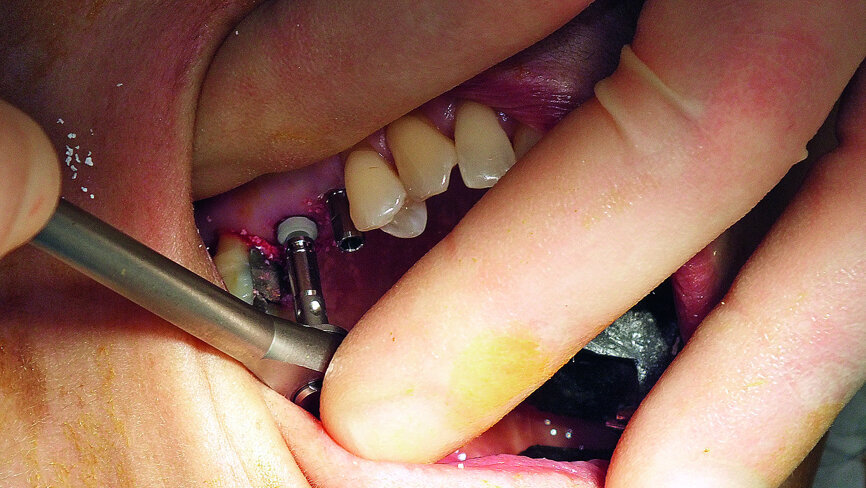

Computer-guided dynamic navigation with Navident by ClaroNav was used in the preparation of this case. Scanning and planning took place during the assessment visit, 48 hours before implant surgery. A NaviStent was fabricated and a fiducial marker attached, prior to the CBCT scan. Fabrication of the NaviStent is quick, easy and takes place chairside, using a unique thermo-plastic material which is moulded directly onto the patient’s existing dentition. The NaviStent is designed and fabricated to ensure a high level of stability, while providing unrestricted access to the planned implant sites.

Fig. 3: Preparation of NaviStent, and drill and jaw tags immediately prior to surgery.

Treatment was carried out under local anaesthesia. The flapless procedure resulted in minimal trauma to the gingival tissue overlying the ridge. The previously constructed NaviStent, and the drill tag and jaw tag supplied by ClaroNav, were prepared immediately prior to surgery (Fig. 3). In accordance with the Navident protocol, the axis of the drill and tip of the pilot drill were calibrated (Figs. 4 and 5) and verified before site preparation commenced (Fig. 6). Using computer-guided surgery, the pathway of the drill could be followed clearly on the computer screen positioned in front of the patient (Fig. 7). Approximately 1 mm of bone was left intact in the upper right first molar site ready for the sinus lift. Navident provided visual confirmation of the position of the drill tip to accurately gauge the correct depth (Fig. 8). Preparation continued using a 3.5 mm drill bit, which, again, was calibrated and verified before use (Figs. 9 and 10).